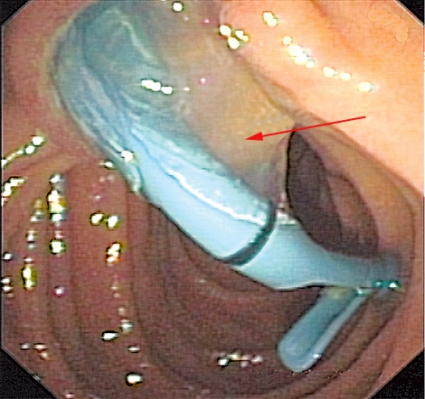

Fall 2. En 34-årig man från Tunisien sökte vård för buksmärta och hög feber. Patienten var ikterisk och visade tecken till gallstas. Antibiotikabehandling inleddes då den kliniska bilden talade för kolangit. Utredning med ultraljud och DT påvisade två cystiska förändringar i levern (5 respektive 6 cm stora), båda såg ut som ekinokockcystor. Blodprov visade stegrat CRP och eosinofili. Serologisk diagnostik bekräftade diagnosen. Gallvägarna avlastades med stentning via endoskopisk retrograd kolangiopankreatografi (ERCP) på grund av en intrahepatisk striktur (Figur 2). Behandlingen förbättrade initialt kolangiten, men patienten fick flera recidiv.

Radiologisk utredning av ekinokockcystor har flera målsättningar. Den ska bidra till diagnostiken och till en anatomisk kartläggning av utbredning och eventuella komplikationer, bedöma cystans viabilitet och underlätta preoperativ planering. Den radiologiska diagnostiken av ekinokockcystor i levern har centrerats runt ultraljud men har på senare tid ofta ersatts med DT och MR. Radiologiska fynd som talar för ekinokockcysta utgörs framför allt av cystvägg med dubbelkontur, multivesikulärt utseende och väggförkalkningar (talar för inaktiv cysta). Viktigt att komma ihåg är att kalcifiering av väggen förekommer inte bara vid inaktiva (CE4 och CE5) cystor utan även i upp till 50 procent vid alla stadier [7]. WHO-klassifikationen av ekinokockcystor grundas på ultraljudsundersökning men kan överföras till antingen DT eller MR [2, 3]. Cystans relation till gallvägar, kärl och extrahepatisk vävnad bedöms enklast med DT eller MR. Om fistulering till gallvägar misstänks kan MR med kolangiopankreatikografisekvenser och i vissa fall endoskopisk retrograd kolangiopankreatikografi (ERCP) bidra till noggrann anatomisk kartläggning inför planerad resektion [8].